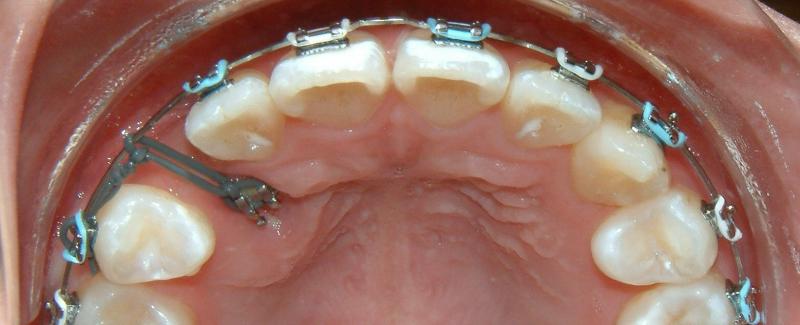

In the 4th post-op visit (3 months after the surgery), the forced-eruption is again activated. This time is by using a piggyback mechanics. The progress of tooth eruption is shown in Fig. 23. Note that the crown of the tooth (lower left canine) is surrounded by healthy gingiva.

Fig. 23 Fourth post-op visit, 3 months after surgical exposure; activated forced eruption (progress)